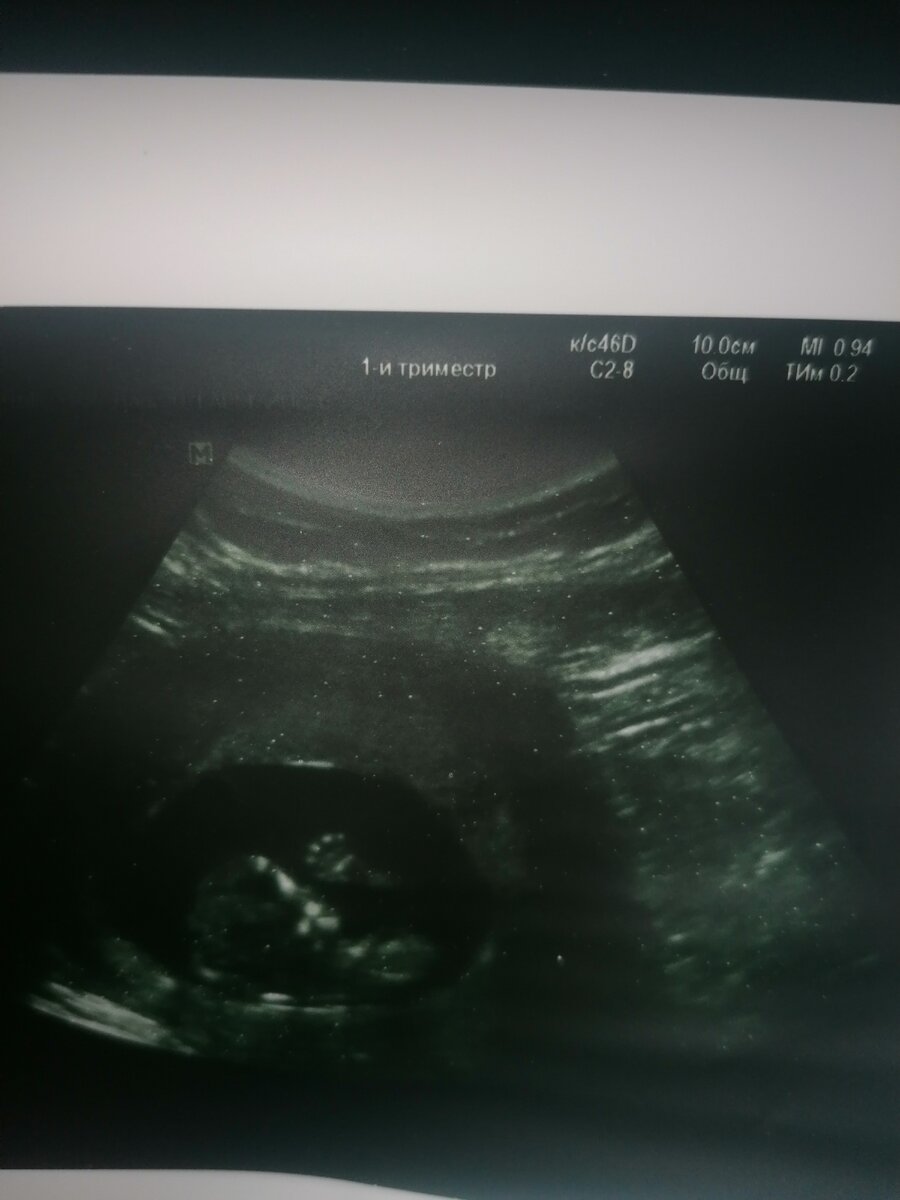

Вот малыш машет ручкой ;)

УЗИ было, но пока неизвестно кто там. Вначале я была в депрессии и не представляла,как я справлюсь со всем этим. Куда мол ещё детей.